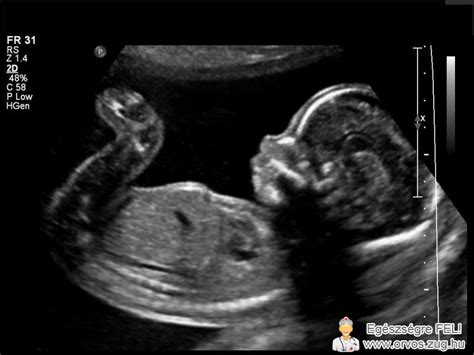

Az ultrahangos vizsgálat során az orvos egy sötét foltot lát a méhben, amely a petezsák, de hiányzik belőle a szikhólyag vagy az embriócsomó. Ez a diagnózis általában a 6. és 7. terhességi hét környékén válik biztossá, amikor már látszódnia kellene a szívműködésnek. A petezsák mérete ebben az esetben nem mindig arányos a terhességi kornak megfelelő fejlődéssel. Például egy 33mm x 22mm méretű petezsákban sem feltétlenül található embrió, ami aggodalomra adhat okot.

Az üres petezsák megállapítása nem mindig történik meg egyetlen vizsgálat alatt, és ez az a bizonytalanság, ami lelkileg a legmegterhelőbb a kismamák számára. Ha egy nő túl korán, például az 5. héten megy el nőgyógyászhoz, előfordulhat, hogy még csak egy üres petezsák látszik, de ez teljesen normális ebben a szakaszban. A kritikus pillanat akkor jön el, amikor a petezsák átmérője elér egy bizonyos méretet - általában 25 millimétert -, de továbbra sem látható benne szikhólyag vagy embrió. Ebben a fázisban a diagnózis már szinte biztos. Az orvosok gyakran néznek sorozatos béta-hCG szintet is a vérből, hogy lássák a trendet.